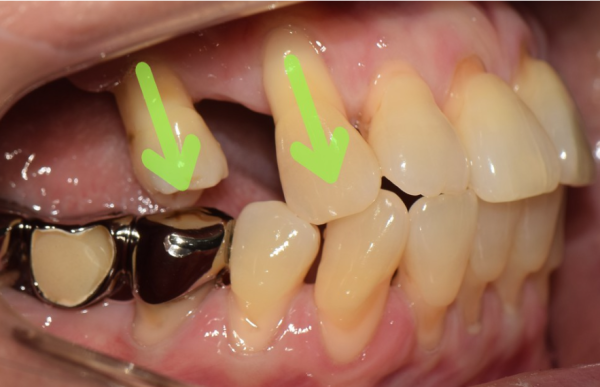

이 환자분은 어금니를 발치하고 시간이 오래되신 분이신데요.

임플란트를 심으려 했지만 쉽지 않다는 이야기를 들으시고, 저희 태평역치과 더서울치과를 찾아주셨습니다.

보이시는 것 처럼 치축이 앞으로 쏠려있고, 앞니도 뿌리가 많이 드러나 있었습니다.

그리고 어금니를 보시면 잇몸뼈가 녹아서 골폭이 줄어들어있습니다.

This patient has had his molars removed for a long time.

After hearing that it was not easy to plant implants, he visited our Taepyeong Station Dental Clinic The Seoul Dental Clinic.

As you can see, the teeth are leaning forward, and the front teeth are also showing a lot of roots.

And if you look at the molars, the gum bones are melted and the bone width is reduced.